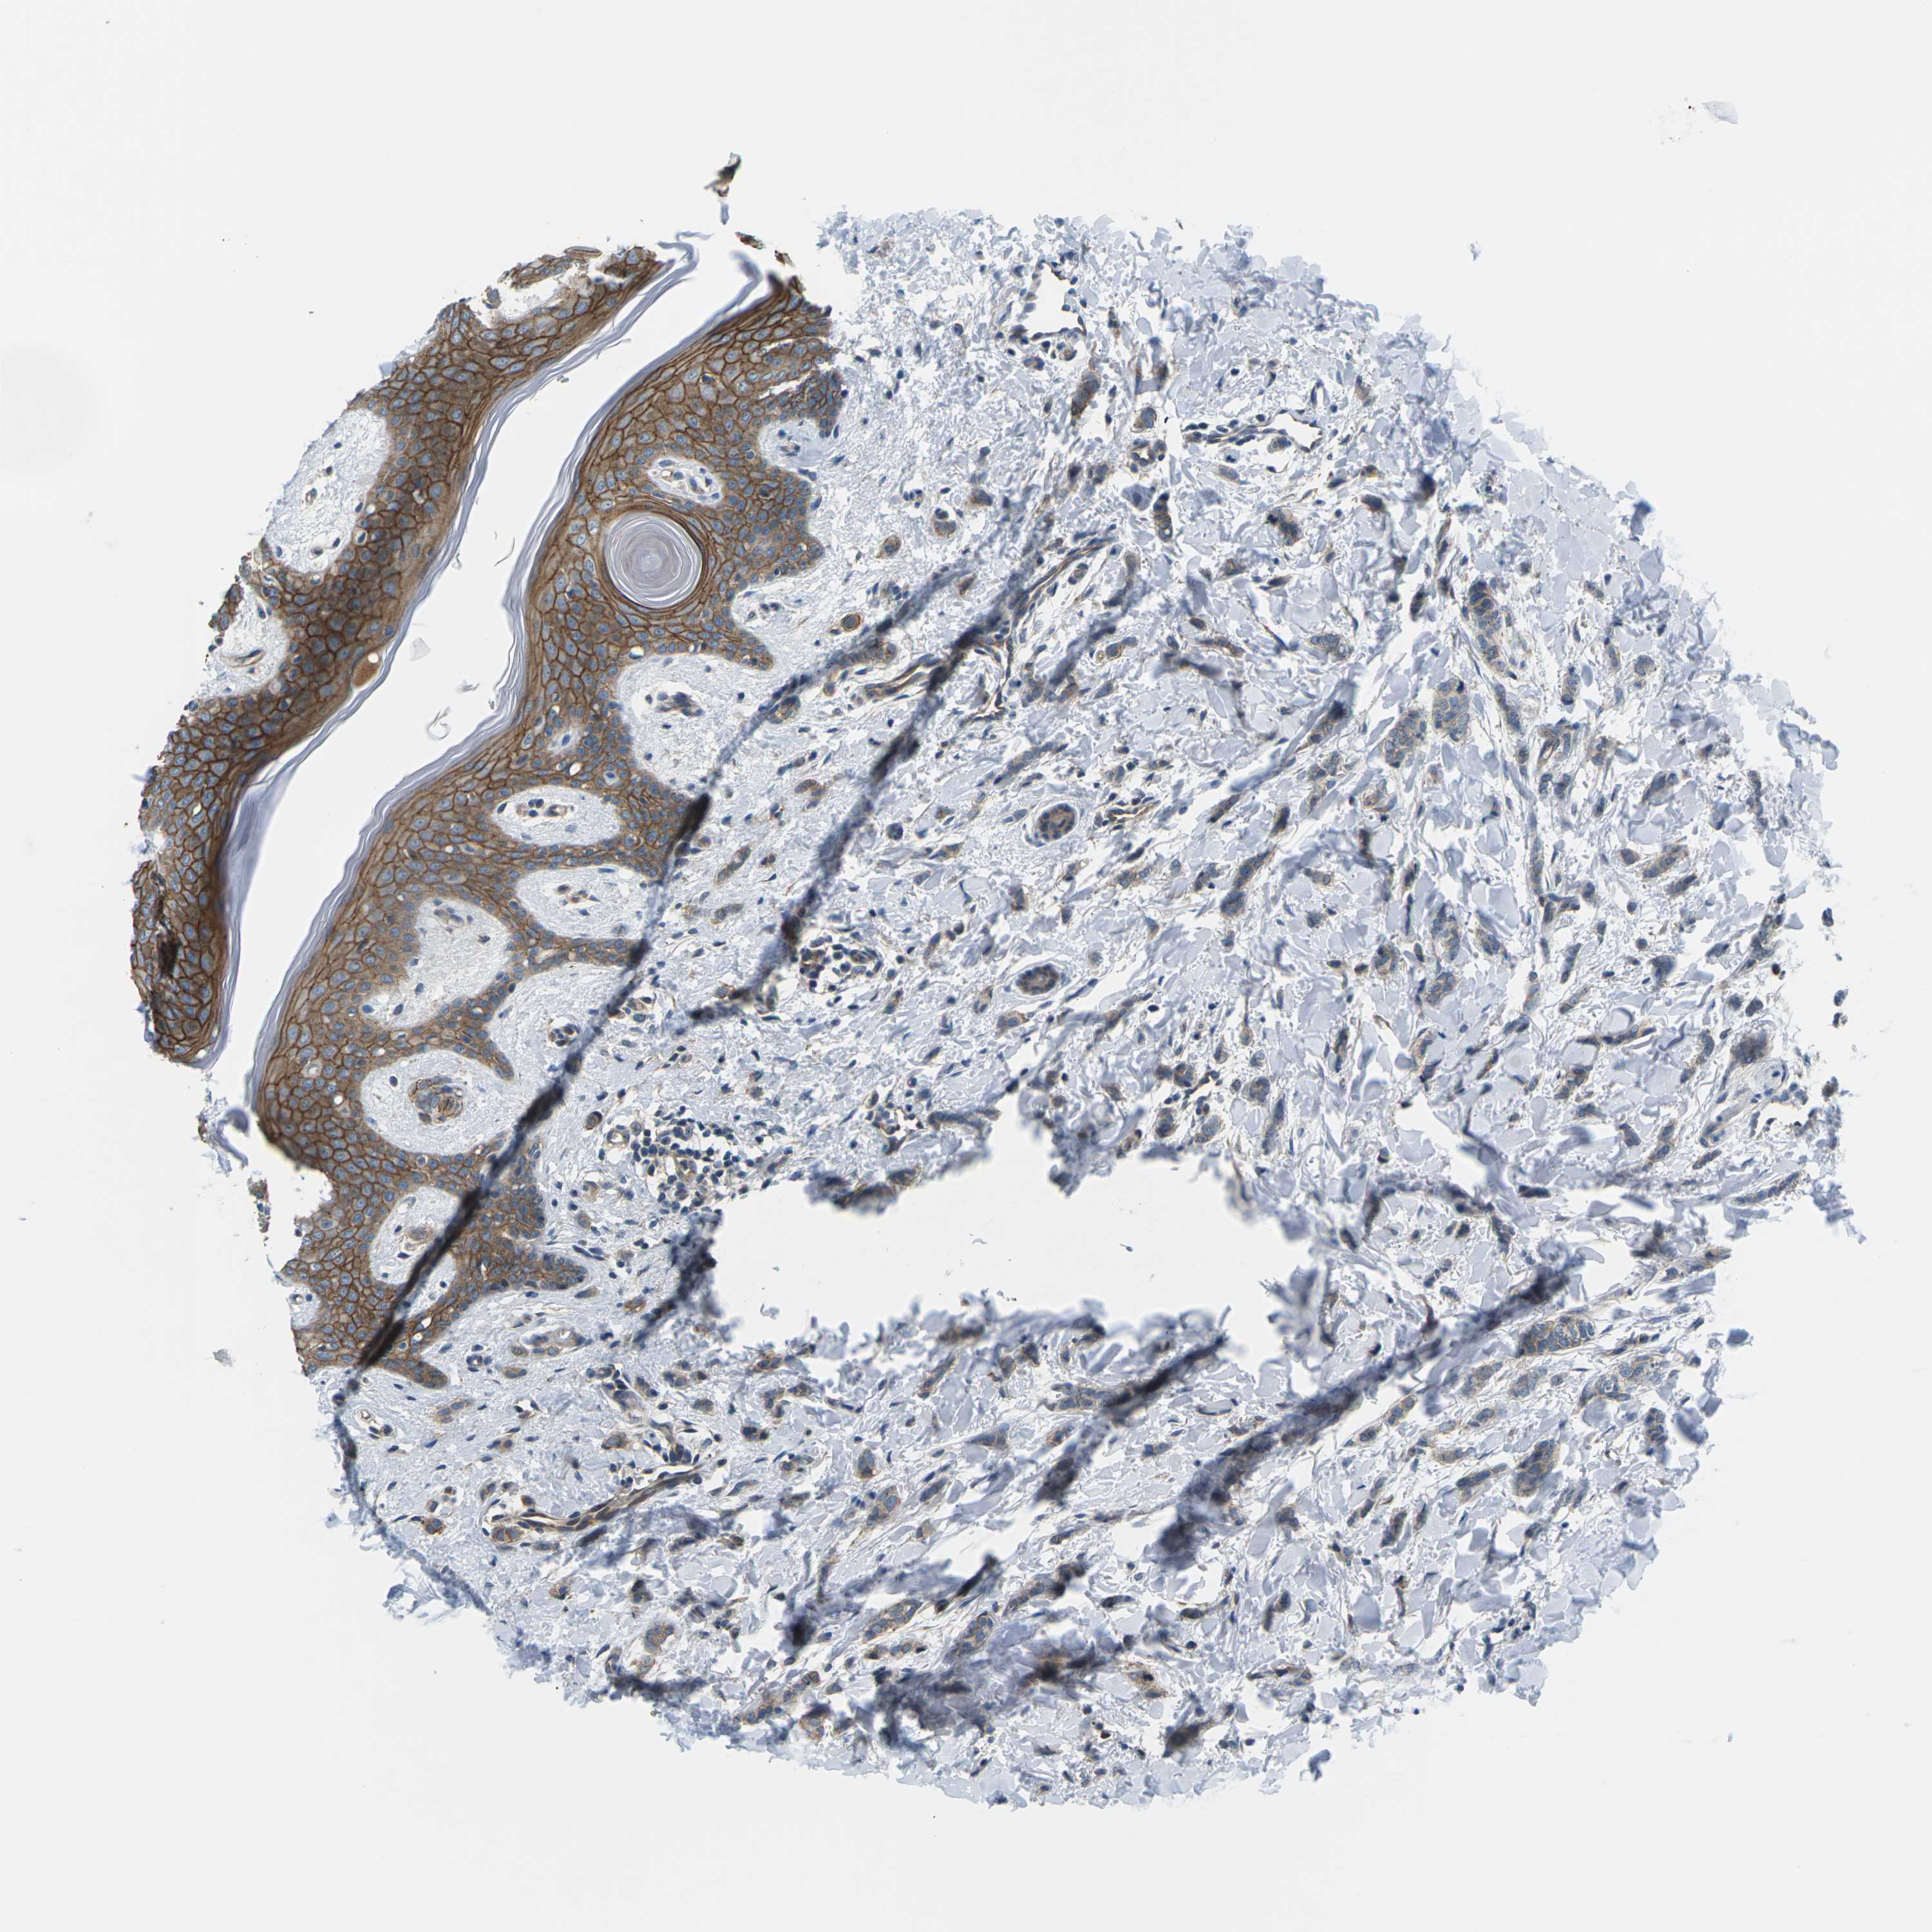

BRCA TCGA BRCA VALIDATION PROTEIN EXPRESSION